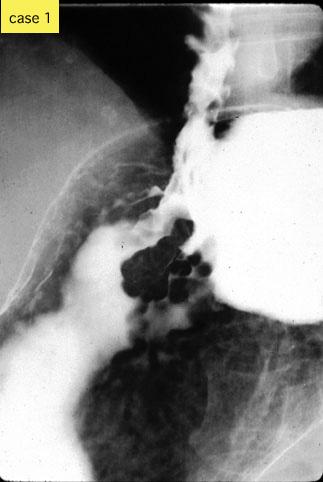

疾患(病理主体)の分類腫瘍様病変/静脈瘤

部位(臓器別)胃(部位)/噴門

検査方法X-P

病変の最大径(ミリ)30〜34